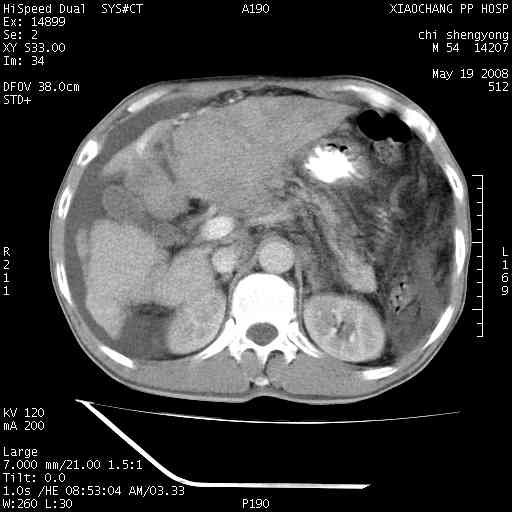

以下是引用zjzjr在2008-5-21 10:52:00的发言:[br]肝左叶巨块型肝癌伴门静脉左支瘤栓形成.肝硬化、腹水,胃底静脉曲张,脾术后改变。

以下是引用随光逐影在2008-5-21 16:20:00的发言:[br]1)肝左叶肝癌伴门静脉左支瘤栓形成,腹膜后淋巴结转移。2)肝硬化、腹水、胃底静脉曲张。3)胆囊炎。4)脾脏缺如,为切除术后所致。